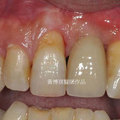

前牙植牙補骨手術範例 瀏覽34 推薦0

Befor 瀏覽33 推薦0